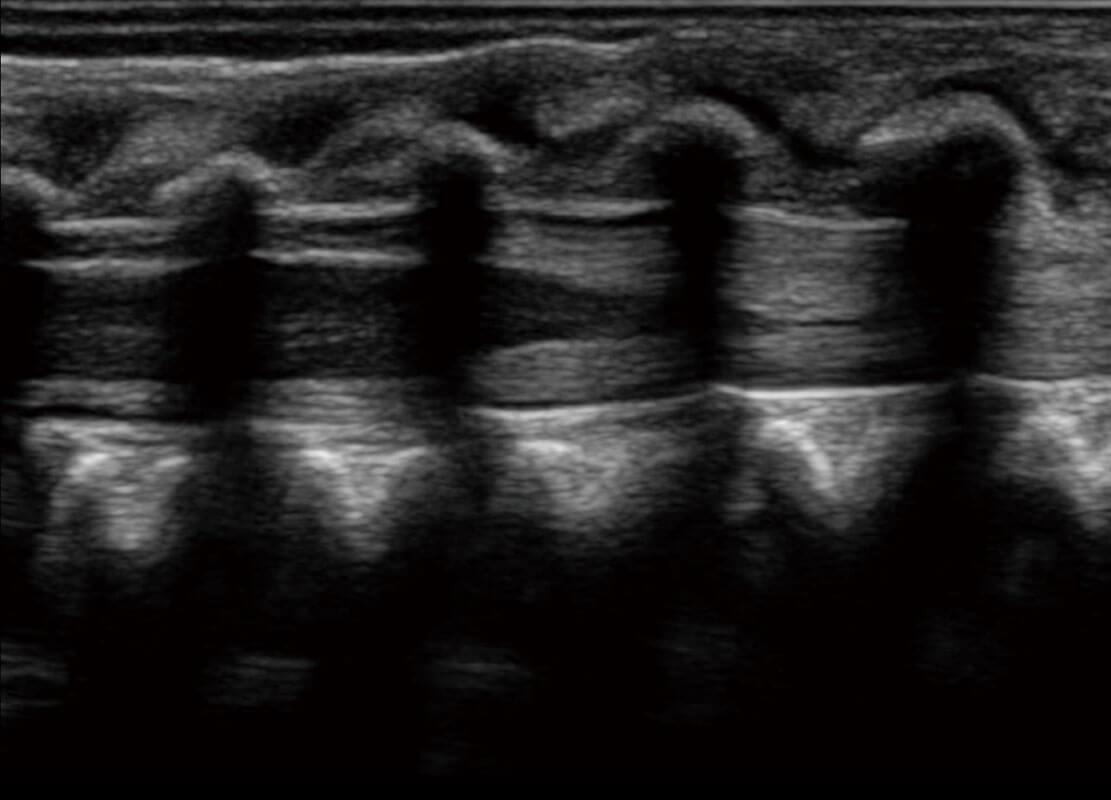

乳腺超声 / 新生儿

P60搭载宽频带线阵探头、宽景成像、弹性成像技术,为您提供乳腺全面应用方案。P60支持高频相控阵探头、线阵探头、腹部高频探头、腹部微凸探头等,丰富的探头群搭载敏感的彩色血流成像,适用于新生儿多种脏器检测要求,满足新生儿筛查需求。

• 新生儿肝血管癌

• 新生儿脊髓圆锥

• 新生儿心脏